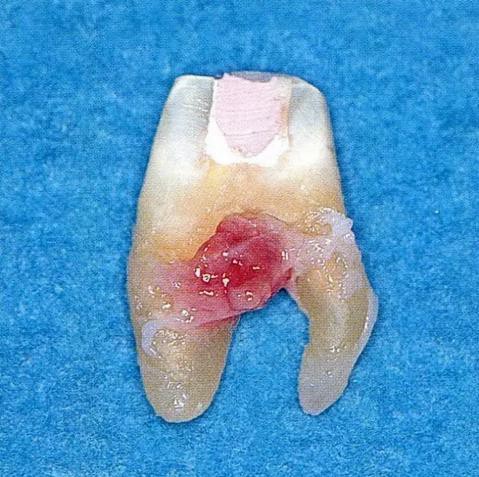

▼圖6-1 下頜第一后磨牙的頰舌間存在III度的根分叉病變,預(yù)在進行牙根分割后保留遠(yuǎn)中根。

▼圖6-2 中下頜第一后磨牙雖然切除了一半,但是遠(yuǎn)中根也有2根分根,所以不得已拔除(被拔除遠(yuǎn)中根的近中面觀察)。